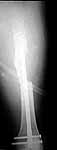

30 y/o man in head-on MVA 12/22/03 sustaining grade II open left femoral midshaft fracture (treated with appropriate staged debridement and retrograde statically locked IM nail), left lateral split tibial plateau fracture (treated with reduction and percutaneous cannulated screw fixation) and comminuted left femoral neck fracture (treated with open reduction and non-compression screw fixation). All initial treatment at another institution and patient recently came to me for follow-up care (he was travelling out of town when he was injured). He has a large (7cm) defect of lateral half of femoral shaft fracture which I plan to pack with a ton of bone graft next week (open fracture site soft tissues healed nicely without sign of infection).

Only small part of femoral shaft fracture visible on one xray. I would be interested in seeing xrays of the shaft fracture. I would be hesitant about bone grafting the femoral shaft fracture early. It might heal. Femoral neck fracture is going to be a problem. I agree, in varus and almost appears with some distraction at the fracture site. I do not think anything now will significantly increase the chance of salvage. I would suggest observation over a reasonable period of time while on crutches, documentation of healing or lack of healing with CT or tomogram (hard to get as the machines are fewer and fewer), then definitive treatment of what is left at the hip. Not an agressive approach but one that gives a 30 year old a chance to heal given how he was initially treated.

I agree that most femoral shaft fractures (even with defects) don't need grafting, but without inclusive films it's difficult to make an opinion regarding this shaft defect.

The issue of the shaft is harder to tell from the images, but could be addressed concurrently or seperately, based on dedicated imaging.

surgeon. Attached are intra-op films of neck and films of shaft (not great,

but show the cortical defect). Any further input is invited and welcome.